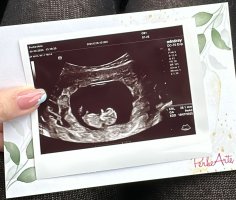

Käytiin varhaisultrassa Pihlajalinnassa 18.11. Kuukautisten mukaan oli 6+5, ultran mukaan 6+4 ja syke näkyi. Viime kesänä ensimmäinen raskauteni päättyi nt-ultrassa todettuun tyhjään kohtuun, mikä oli suuri järkytys meille, kun luultiin kaiken olevan ok. Siksi oli selvä, että heti kun on mahdollista, niin käymme tarkistamassa onhan siellä kohdussa nyt joku. Nt-ultra on vasta 31.12., mutta emme ole ajatelleet käydä ennen sitä toista kertaa. Kerrotaan sitten muille vasta tammikuussa, jos kaikki on ok seulontatulosten jälkeen.